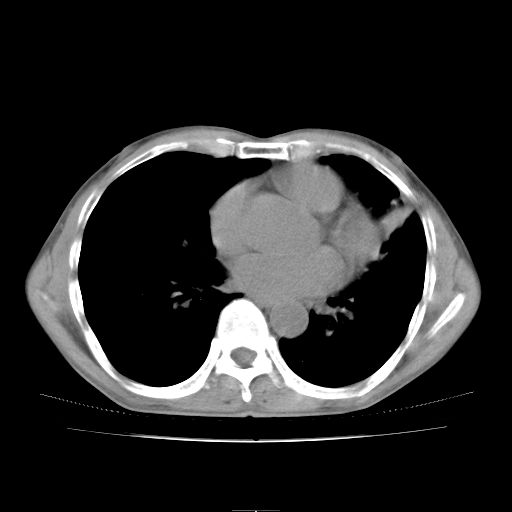

标题: CT25795:感冒后反复咳嗽两月余,痰中带血半月余。X诊断“肺 [打印本页]

标题: CT25795:感冒后反复咳嗽两月余,痰中带血半月余。X诊断“肺

1.双肺肺梗塞(理由:病灶呈三角形,与胸膜相连且局部胸膜肥厚,左心室增大)伴肺感染。

2.一元论双肺感染。

肺梗塞虽然有创意,但不现实。我考虑感染性病灶。

考虑两肺感染性病变,左肺上叶舌段肿瘤性病变待排;建议抗炎治疗后复查。